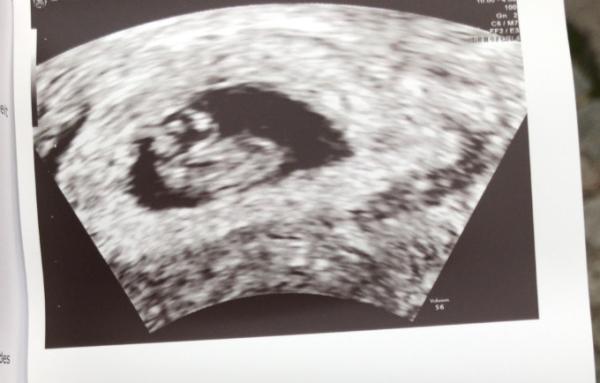

Hallo alle zusammen Befinde mich jetzt bei ssw 7 +5 ..Wahnsinn wie schnell die kleinen im Bauch wachsen .Dies ist mein 3 Kind und immer wieder ein Wunder ET Termin 20.6 Wer noch ?

Bild zu Ultraschall 😍 - Forum fĂŒr Juni - Mamis